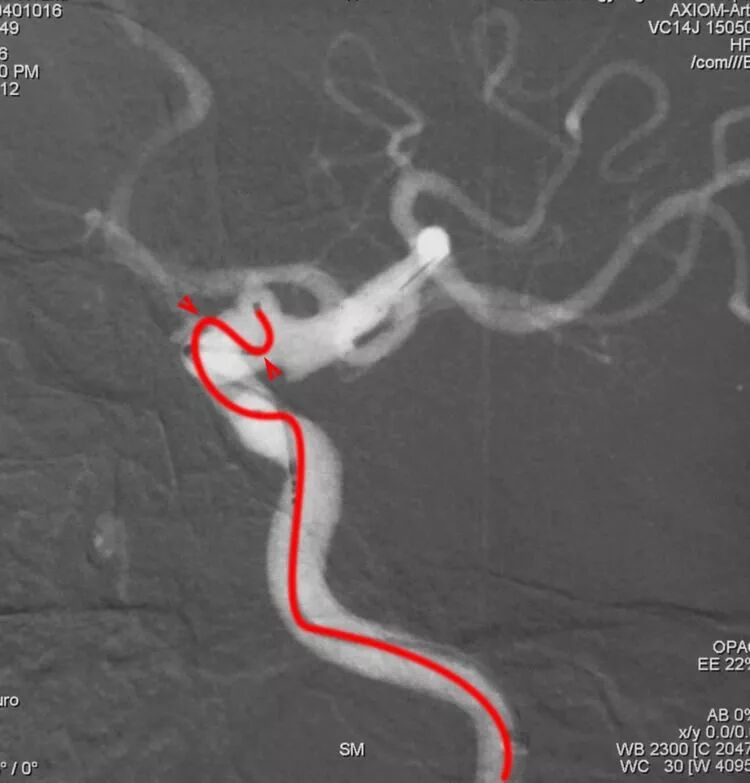

垂体上动脉瘤,起自颈内动脉虹吸弯前膝稍远心端,向后下内方生长,如果用Echelon10微导管栓塞,则需用塑形针把微导管头端塑成猪尾形。当然,如果追求更精准,则需塑一个立体弯儿,且按下不表,后回书中自见分晓